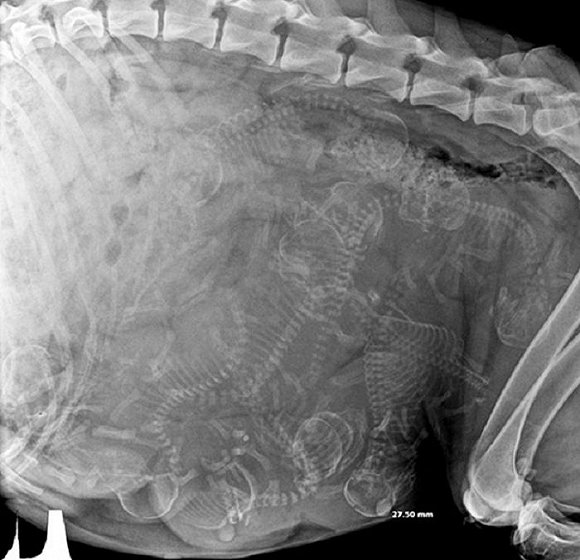

可爱又毛骨悚然 怀孕动物的X光片

人类之间分享母亲肚子里胎儿的X光片是一件非常常见的事情,但是,纵使你觉得自己对X光片已经见怪不怪,在看到了下面这些怀孕动物的X光片后你仍旧会说"哦我的天哪"。

以下就是一些动物在怀孕时的X光片。

3. 狗